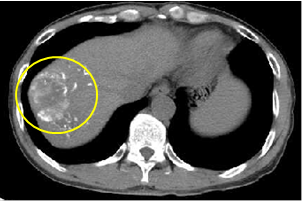

术后1个月CT平扫影像可以在肿瘤部位看到白色光亮微球沉积影,表明显影栓塞微球具有良好的持续显影能力,可作为标记物引导后续的治疗如消融治疗、粒子植入、穿刺活检等。